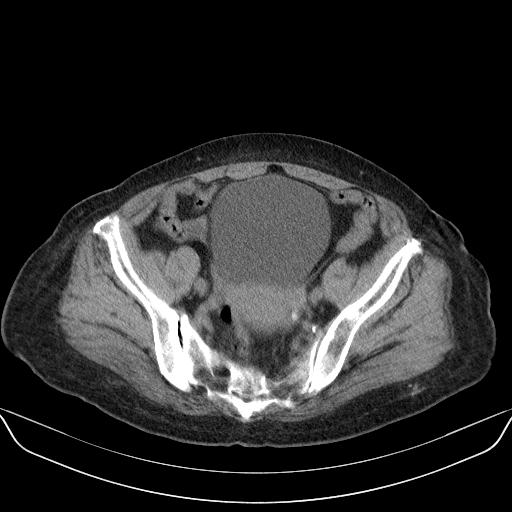

以下是引用yuhongjun在2010-3-12 6:32:00的发言:[br]回肠末端间质瘤,不除外阑尾粘液囊腺瘤,臀部注射性肉芽肿钙化. [br] [br]